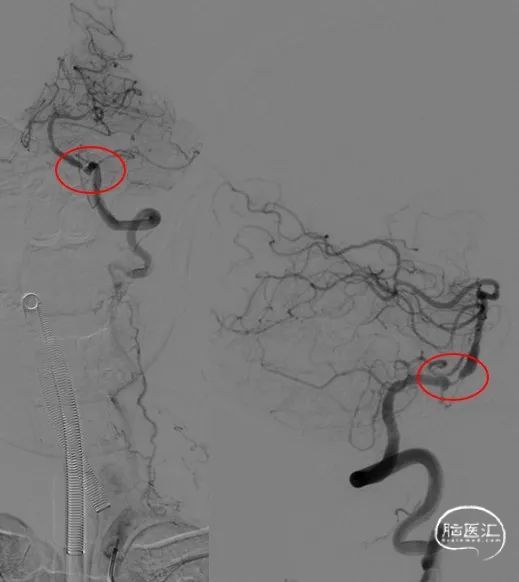

复查DSA:左侧椎动脉V4段重度狭窄。

病变部位:左侧椎动脉V4段

远端正常血管直径(mm):3.6

狭窄处最小直径(mm):0.55

病变长度(mm):8.15

狭窄度(%):84.72%